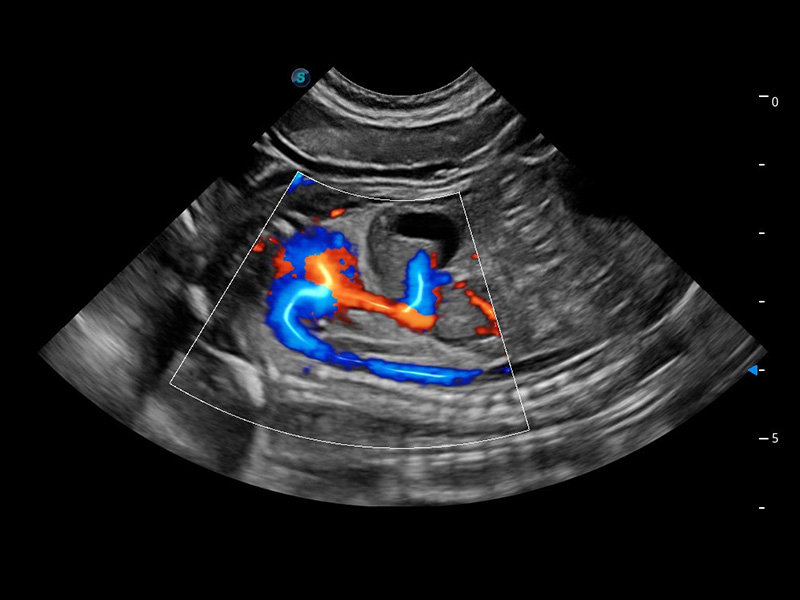

ProPet 60 作为一款高端台式动物超声设备,为动物医生的日常诊断提供了一系列贴合动物临床需求、解决临床实际问题的高级成像功能。凭借全系列高清探头,满足医生对腹部、心脏、生殖、浅表、肌骨等成像的所有需求,切实帮助您提升检查效率,提高诊断信心。

兽用彩色多普勒超声诊断系统

动物是人类最亲密的朋友和最值得信赖的伙伴。db真人体育官网也一直致力于探索动物专用的超声影像解决方案。 全新推出的ProPet系列,是db真人体育官网在动物超声影像智能化、专业化、精准化的一次跨越式革新。动物不能用言语来表述自己的不适,通过超声影像,ProPet系列搭建了动物医生与不同物种沟通的“桥梁”,为动物医生注入了“治愈之力”。